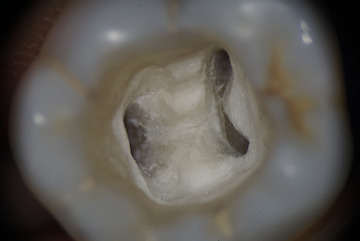

歯の根は長いですので、ピントを奥に合わせるとこのような感じになります。

マイクロスコープを使用することで、最大約25倍に視野を拡大でき、肉眼では分かりにくい、複雑で細い根の形を確認することができます。